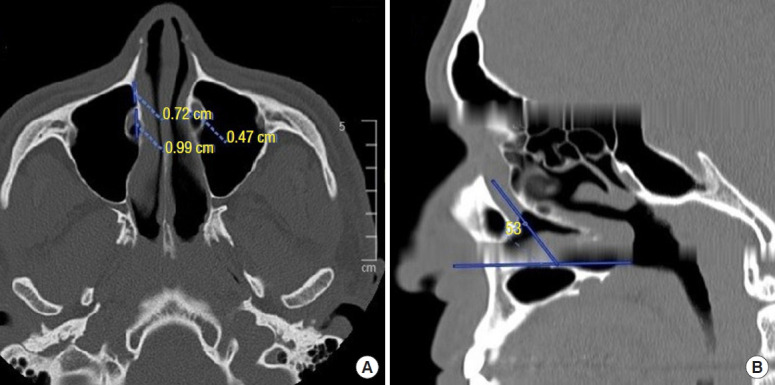

Methods: One hundred paranasal CT scans were included in the study. For all subjects, axial images were obtained, and multiplanar reformats were used to obtain detailed views in the coronal and sagittal planes. The width of the PLW, the width of the nasolacrimal duct (NLD), and the angle between the axis of the NLD and the hard palate were measured and graded.

Results: In 100 CT scans (200 sides), the mean PLW width was 5.6± 2.4 mm (range, 0-11.15 mm), the mean NLD width was 6.38± 1.84 mm (range, 1-11 mm), and the mean angle between the axis of the NLD and the hard palate was 68.6°± 6.77° (range, 54°-83°). There were no significant differences between sides or genders for any of the measurements.